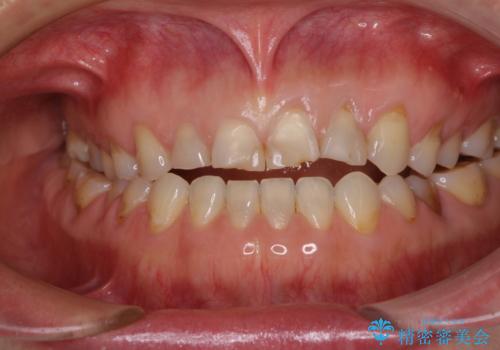

- 咬み合わせと度重なる応急処置の繰り返しにより、前歯がガタガタになってしまったとのことで来院された患者様です。

4本の前歯が気になっていたので、全てをオールセラミッククラウンにて補綴治療を行うこととしました。

4本とも治療前の歯髄の状態は正常でしたが、補綴治療により歯を大きく削ることになるため、歯髄が炎症を起こすリスクがあることを了解いただきました。